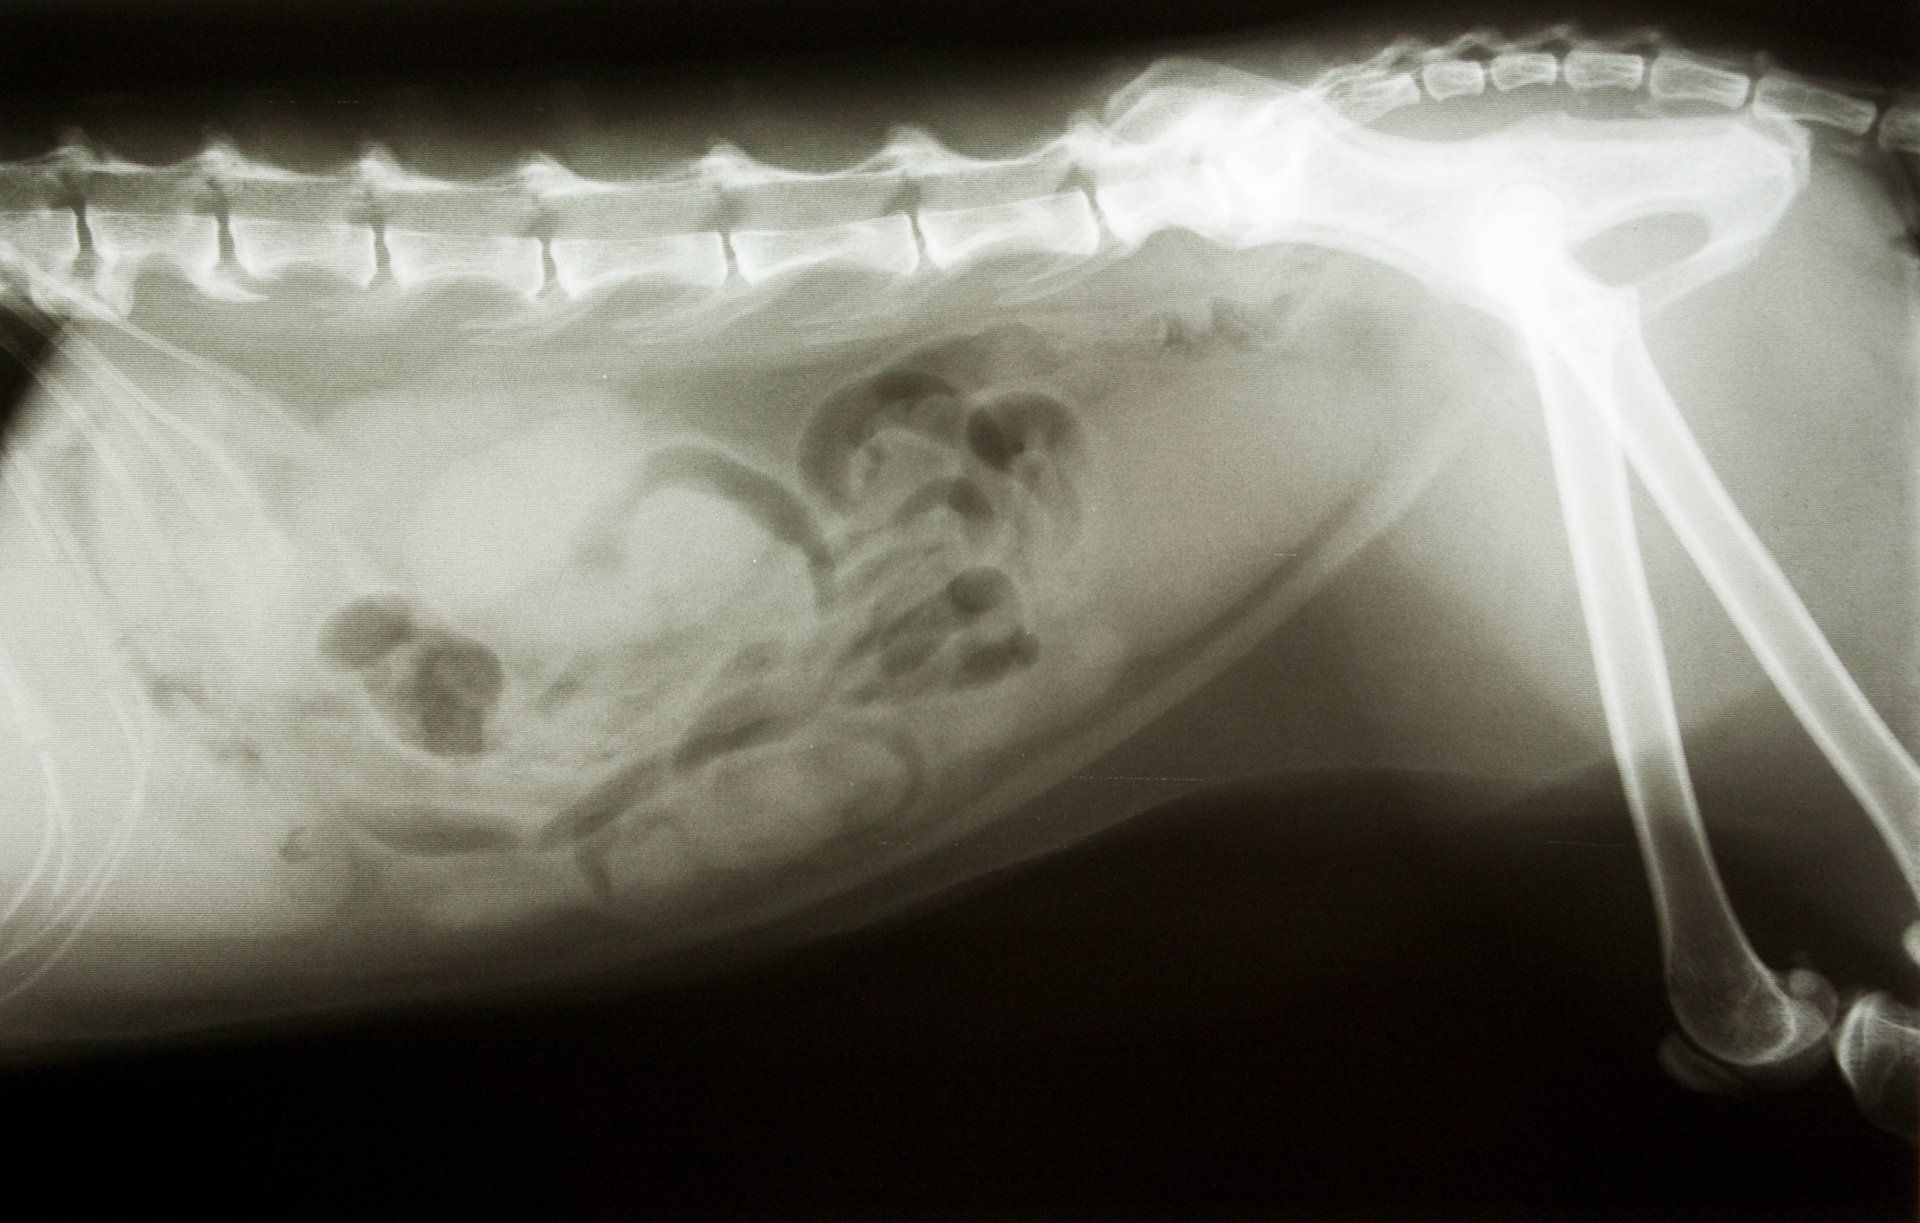

- Röntgen